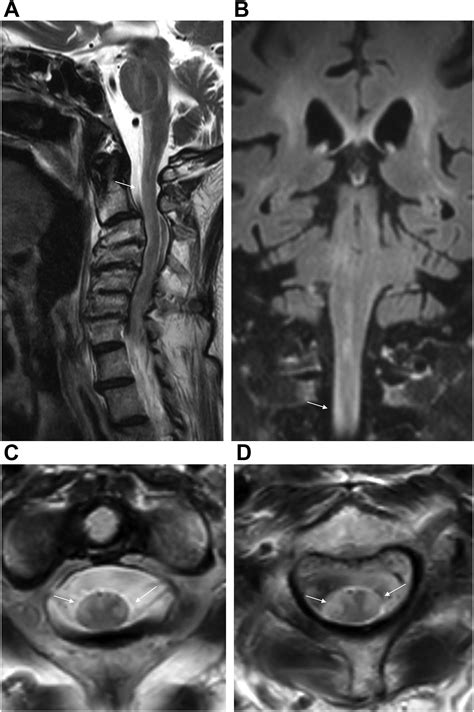

Diagnosing White Matter Disease typically relies on advanced imaging techniques rather than just clinical observation. Physicians look for specific patterns of damage that distinguish this condition from others like Alzheimer’s or stroke.

MRI (Magnetic Resonance Imaging) The gold standard for identifying white matter hyperintensities (bright spots on the scan indicating damage).

At its core, White Matter Disease refers to a range of conditions that result from damage to the white matter of the brain. This white matter is composed of nerve fibers called axons, which are insulated by a fatty substance known as myelin. Myelin is crucial because it ensures that electrical signals travel quickly and efficiently between different parts of the brain and the spinal cord.